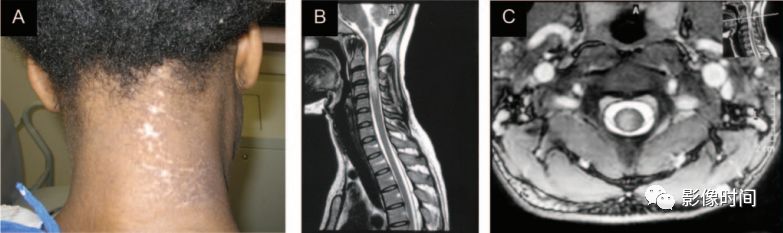

神经梅毒(Neurosyphilis):是由梅毒螺旋体感染中枢神经系统引起,HIV 或 AIDS 发病率较高,确诊需要实验室检查。

MRI:

脊髓内出现长节段 T2WI 高信号

增强扫描出现结节样强化(肉芽肿形成)

邻近脑膜可出现强化

T2WI显示脊髓内长节段高信号,增强扫描出现多发结节状高信号,位于脊髓表面

带状疱疹脊髓炎:患者往往存在带状疱疹病史

发病皮区相对应的单侧脊髓节段受累,T2WI 为高信号

发病皮区相对应脊髓层面出现T2WI高信号